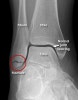

AP, lateral, Mortise view를 보면 대부분의 골절이 진단됩니다.

돌림손상 시에는 거골 바깥쪽 관절면의 골연골성 골절이 일어날 수 있습니다. Mortise view에서 가장 잘 나타나며 복합골절 평가 시에는 CT가 필요할 수 있습니다.

X-ray : 외과 골절(Lateral malleolar fracture)